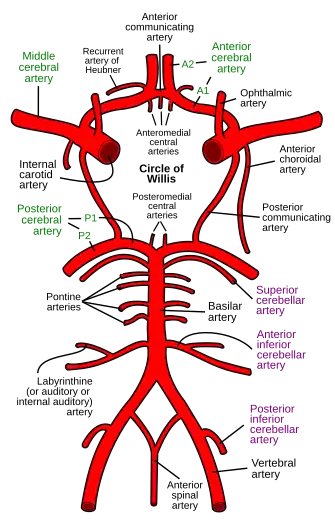

Schematic representation of the arterial circle and arteries of the brain (inferior view). Blood flows up to the brain through the vertebral arteries and the internal carotid arteries. | |

In human anatomy, the left and right posterior communicating arteries are small[1]: 471 arteries at the base of the brain that form part of the circle of Willis.

Anteriorly, it unites with the internal carotid artery (ICA) (prior to the terminal bifurcation of the ICA into the anterior cerebral artery and middle cerebral artery); posteriorly, it unites with the posterior cerebral artery.

With the anterior communicating artery, the posterior communicating arteries establish a system of collateral circulation in cerebral circulation.

The brain is supplied with blood by the internal carotid arteries and also by the posterior cerebral arteries; the posterior communicating arteries connects the two systems. This provides redundancies or collaterals in the cerebral circulation so that, if one system is blocked or narrowed, the other can take over.